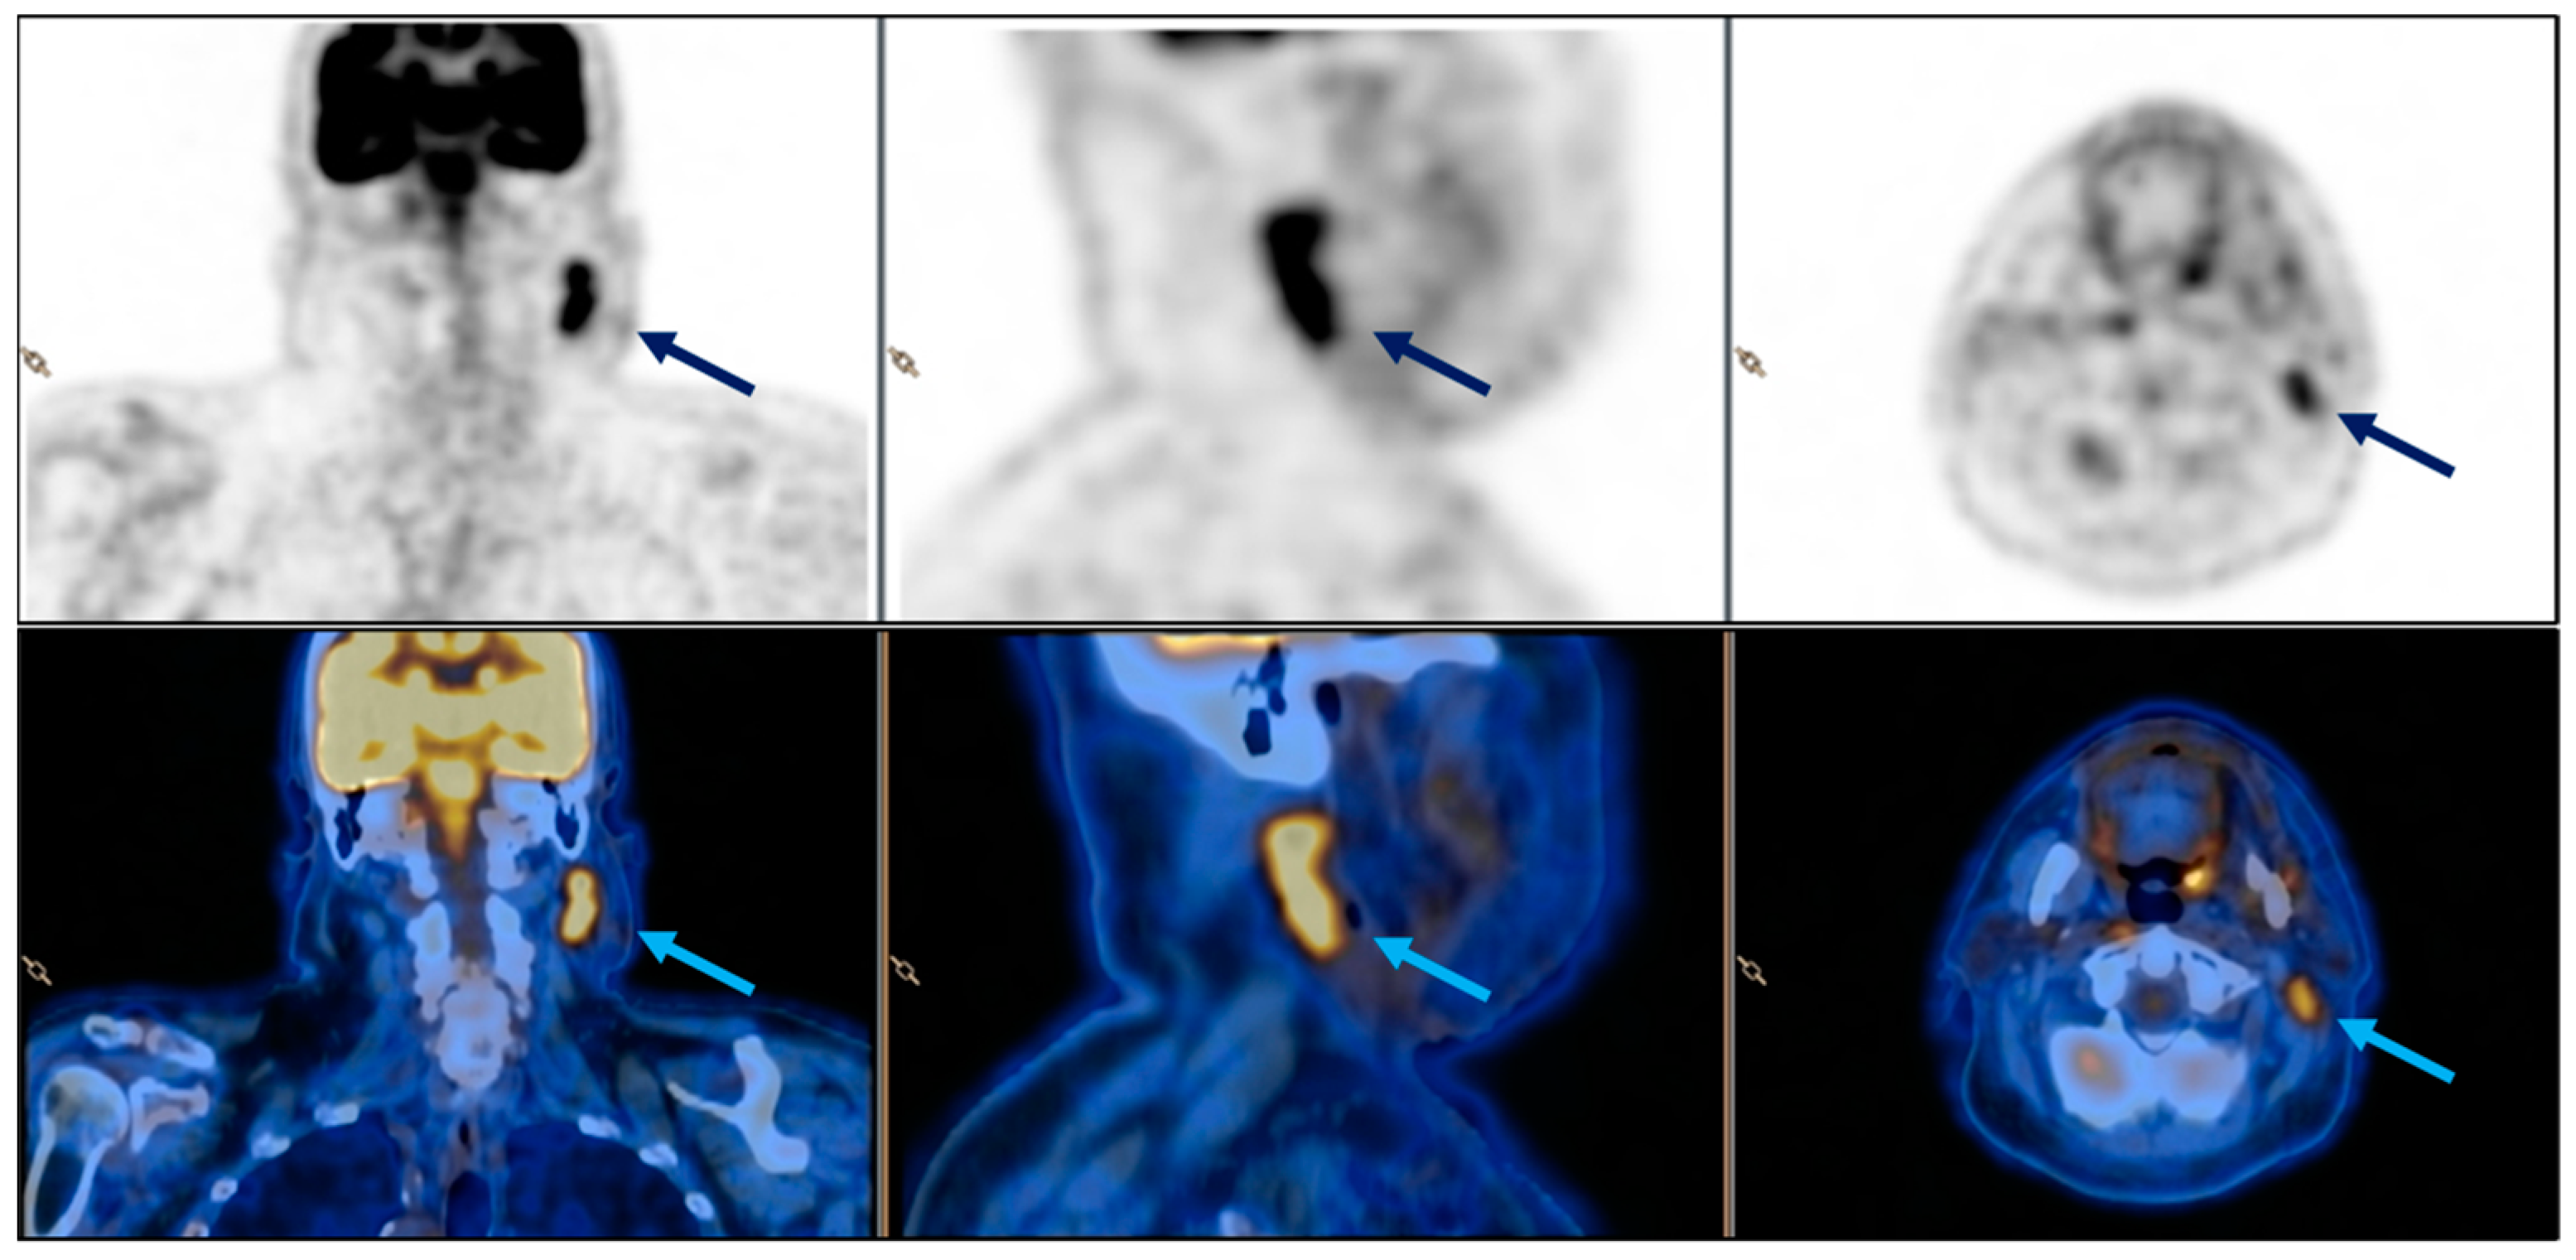

| Presented case 1 | 2024 | Case report | 1 | 78 | F | Maxilla | Tabotamp | Ameloblastoma | Excision of primary tumour | CT + MRI | 15 d | CT + MRI + surgical excison | H |

| Case 1 | Elongated, non-homogenous hyperechogenic formation with an expansive growth pattern | CT (1): Lymphadenopathy […] and exhibited areas of colliquation | Persistent left adenopathy was observed, with no evidence of restricted signal in DWI or post-contrastographic enhancement | Ovoid mass with an elevate 18-FDG uptake (SUV 7, 5) | C (1): Necrotic debris, neutrophilic granulocytes, and rare multinucleated histiocytic giant cells. C (2): Cytological sample revealed the presence of a birefringent material, which was identified as sutures, macrophages, and isolated foreign body-like giant multi-nucleated cells | |